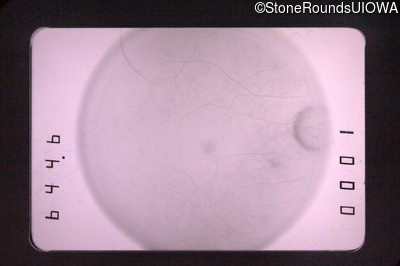

Fluorescein Angiography - Right - 20/30

Exemplar